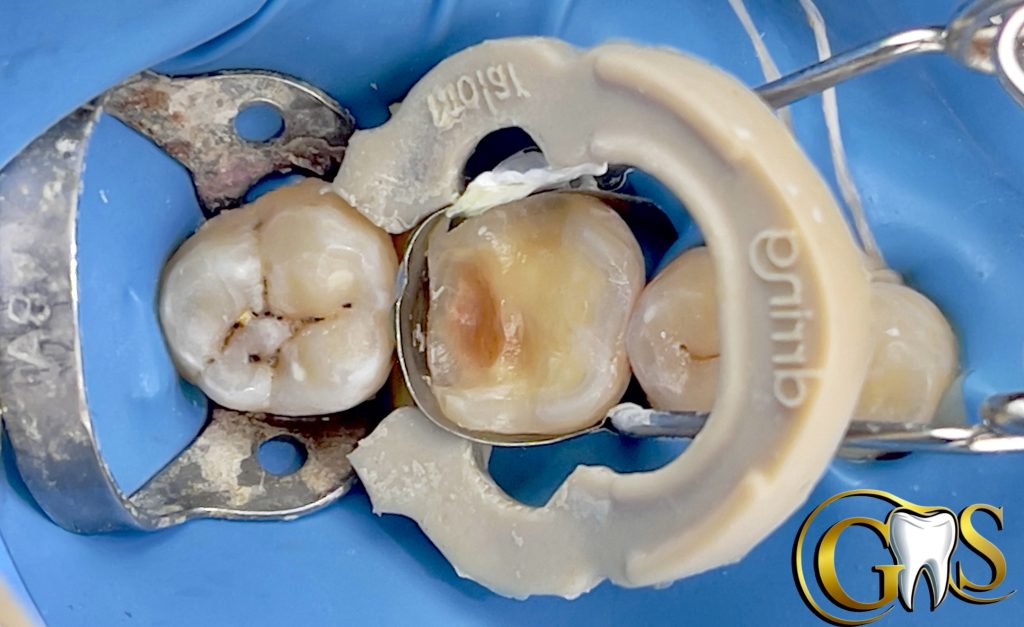

Saving vitality of LR6 (46) with Biomimetic Approach

A 34y female patient camed to our clinic complaining from food stagnation in lower right first molar with no signs of pain .. after diagnosis and sensibility test my decision was to save pulp vitality .

1-cavity optimization

-cuspal reduction

-flaring

-Beveling

-smoothening

-(SCR+PSZ)